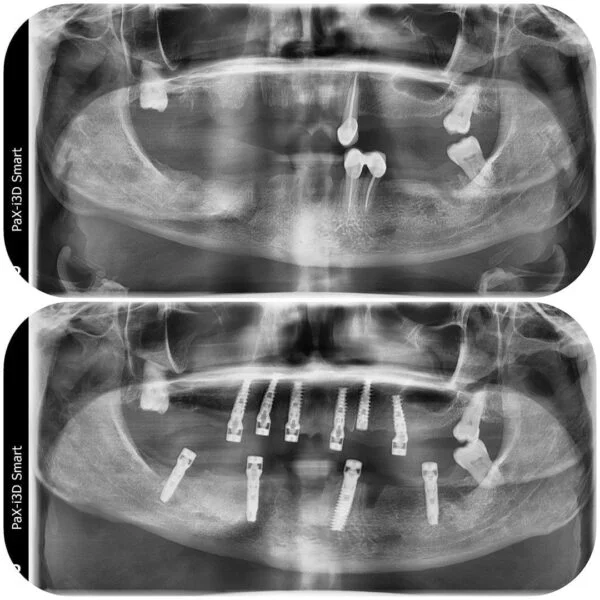

Implantul dentar este adesea recomandat deoarece prezintă foarte multe avantaje, iar, de multe ori, este unica soluție pentru protezarea unei edentații.